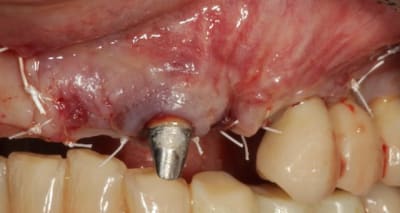

Grosse perte osseuse au niveau de la 23, ROG avec Bio-Oss et autogène dans un rapport 50/50, le tout recouvert pas une BIo-gide maintenu avec de pin's.

Belle chirurgie. J'apprecie particulièrement tes tracés d'incision : on voit que tu mènes une chirurgie réfléchie et le soin que tu portes aux tissus parodontaux est juste. Tu es rigoureux avec les autres mais également avec toi-même et c'est tout en ton honneur !!

Tu sais le lambeau est replacé parfaitement et suturé soigneusement une fois que la chirurgie est terminée : vraiment aucune complication à craindre à ce niveau, surtout pas quand les tissus ont été manipulés avec un tel soin : incision franche, élévation propre, aucune déchirure, suture impeccable.

Désolé pour le retard, je vais essayé de répondre à tout le monde, mettre un implant et faire une ROG de façon predictible dans un cas comme ça c'est impossible, la photo pré-op c'est la dernière ( je ne sais pas pourquoi nonol m'a inversé l'ordre ), à noter que j'ai fait ce design d'incision car 24 et 25 sont des implants et je ne voulais justement pas me retrouver avec une récession.

J'ai utilisé du BIo-Oss et de l'autogène prélevé avec un scraper à la mandibule, le tout recouvert par une Bio-Gide maintenu par des pin's, suture avec du Gore Tex ( e-PTFE ) et du Cytoplast (PTFE )